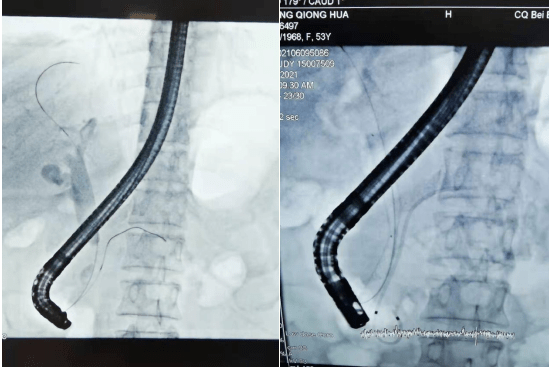

ercp造影图片

胆总管多发结石ercp手术

ercp术中造影显示胆总管下段狭窄

ercp造影见胆总管结石

ercp术中造影提示,结石巨大,给予网蓝机械碎石治疗,碎石成功.